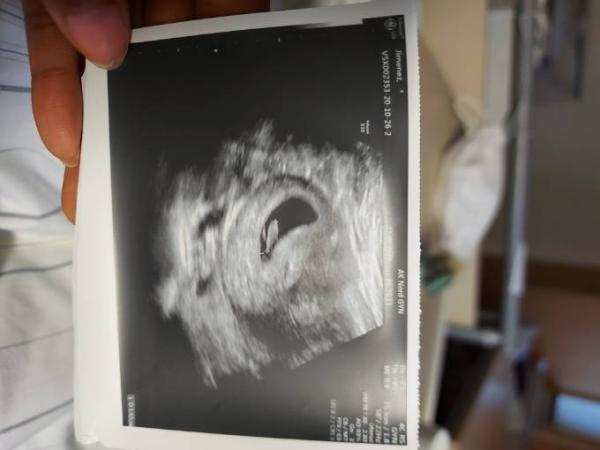

Huhu, na wie war es? Ich hatte meinen ersten Termin statt bei der Gynäkologin im Krankenhaus, aber es gab zumindest noch ein Bild

Bild zu